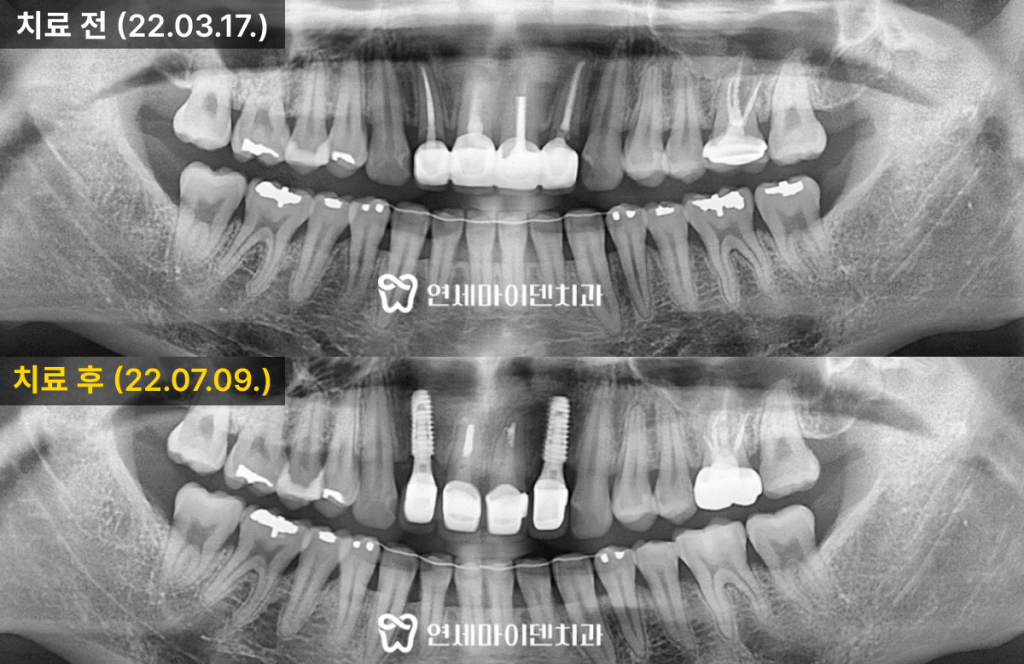

환자분은 오른쪽 아래 어금니의 통증과

흔들림을 주소로 내원하셨습니다.엑스레이 검사 결과, 해당 치아의 뿌리 주변 치조골이

심하게 흡수된 상태로 확인되었습니다.겉보기에는 일부 뿌리가 정상처럼 보였으나,

세균막이 깊이 침투하여 치근 주위의 골소실이

광범위하게 진행된 상태였습니다.이러한 경우에는 신경치료나 치근절제술로는

예후를 기대하기 어렵기 때문에

발치 및 즉시 임플란트 치료를 계획하였습니다.또한 반대편 어금니와 상악 어금니에서도

동일하게 치주염이 진행되어

총 세 부위에 대한 치료가 필요하다고 판단하였습니다.